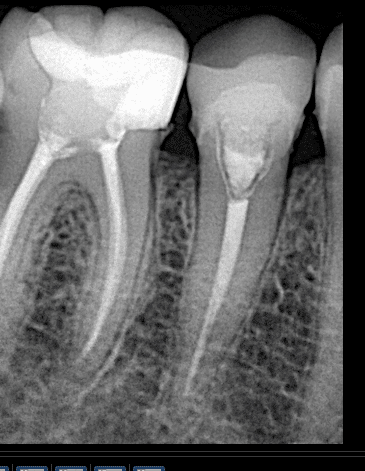

Initial x ray

After preparing the tooth

Final x ray